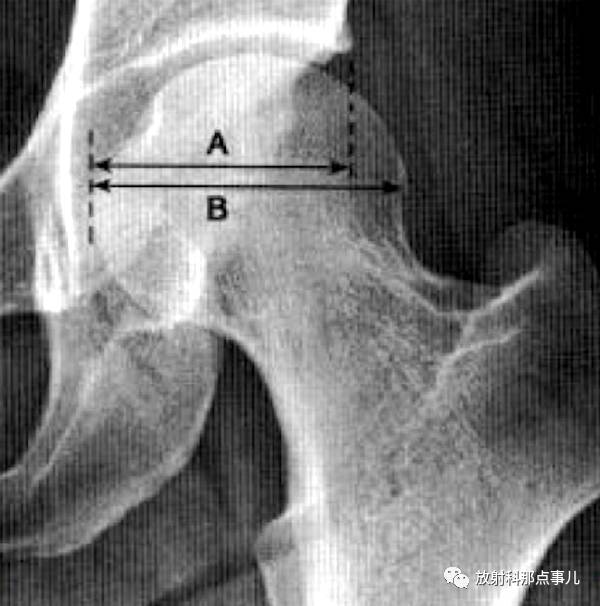

正常时,男13(7-18)mm,68女12(9-18)mm,与ce角配合用于评价髋臼发育

正常时,男13(7-18)mm, 女12(9-18)mm,与ce角配合用于评价髋臼发育情况

正常时,男13(7-18)mm,女12(9-18)mm,与ce角配合用于评价髋臼发育情况